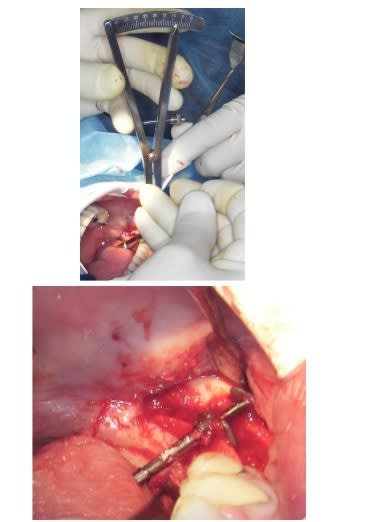

Graphique 1 vyoujt - Eugenol

Graphique 2 hsfukr - Eugenol

Graphique 4 v7qsp9 - Eugenol

Graphique 5 aalb5r - Eugenol

Graphique 6 hf5zh8 - Eugenol

c'est beau...

dommage que tu n'ai pas mis les photos en unitaires on verrait mieux que sur un planche.